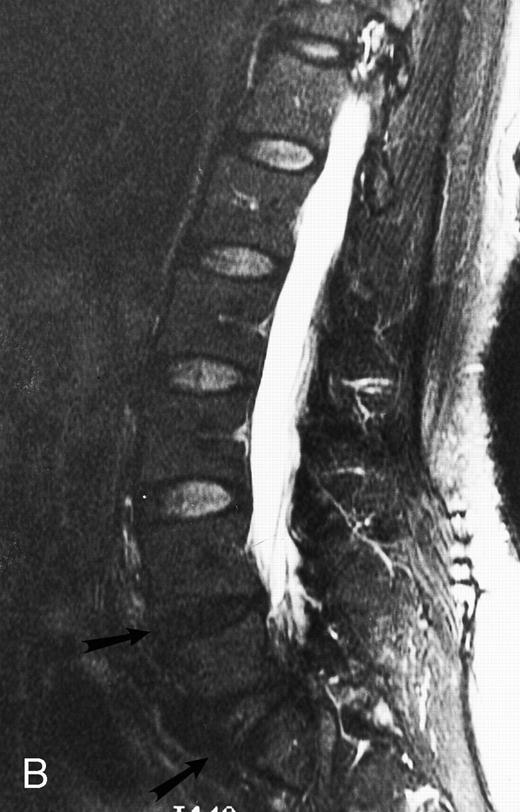

A 38-year-old man with solitary plasmacytoma of L5. Relatively T2-weighted gradient recalled echo (400/21, TR/TE, flip angle 20°) sagittal MR image of the lumbar spine shows bright signal of mass in L5 and extension of tumor into the spinal canal (arrows) with impingement of the thecal sac.